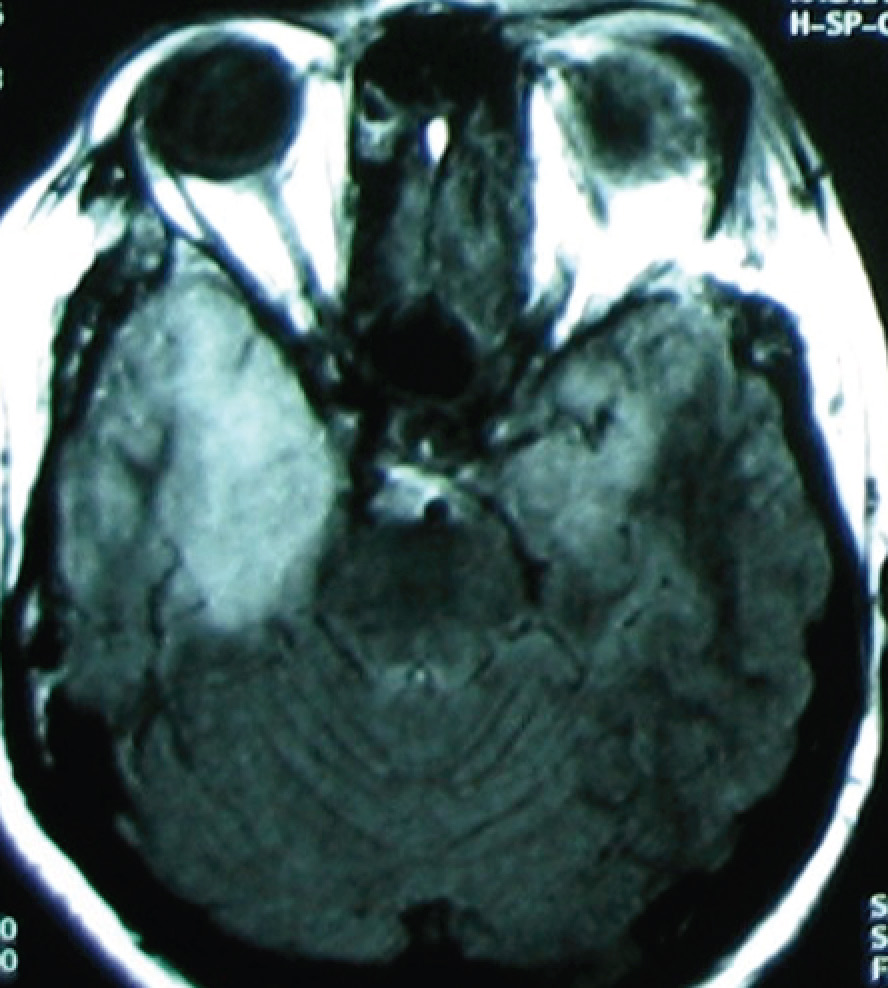

MRI (T2 image) of the woman with fever and impaired consciousness.

Her symptoms are typical of encephalitis, and the MRI shows enhancement of both (right more than left) temporal lobes of the brain. This is virtually pathognomonic of herpes simplex type I (HSV-1) encephalitis. It is unclear at this point in time why the virus acutely infects the brain in a small proportion of patients (but not others). The majority of patients will not have the typical oral-mucosal herpetic vesicles or ulcers that are seen with HSV-1 infection. The diagnosis can be confirmed via lumbar puncture, with cerebrospinal fluid (CSF) sent for HSV PCR. This is in addition to other CSF tests such as CSF analysis, etc (in order to be complete – CSF is much harder to obtain than blood).